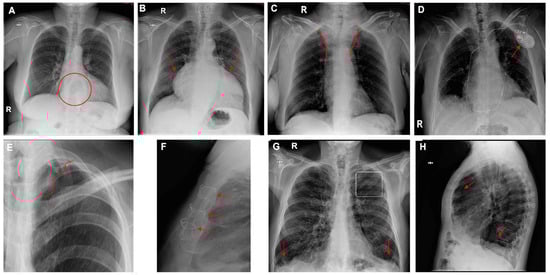

The AI software (Arterys Chest MICA v29.4.0, developed by Arterys, a company based in Paris, France) was the World’s First Online Medical Imaging Platform 100% Cloud native, powered by AI and FDA cleared. It was a clinical application (CE marked as a Class IIa medical device) designed to process thoracic radiographic series and identify five imaging findings (categorical variables): pulmonary nodule, pulmonary opacity, pleural effusion, pneumothorax, and fracture. Each detected finding was localized in the image using a bounding box and was assigned a confidence label, either “positive” (continuous line) or “doubtful” (dashed line). Moreover, the algorithm provided a list of findings not detected in the current radiographic view (Figure 2). All findings were detected by a deep learning model that processed all radiographic views included in the series.

Figure 4 presents several examples of chest radiographs analyzed by the AI.

Figure 4. Chest radiographs with AI analysis (and E,F,H,I with the associated sagittal (E,I), coronal (F), and axial (H) CT images). (A) False doubtful right fractures outlined with discontinuous boxes (they are chronic). (B) False doubtful right pneumothorax outlined with a discontinuous box. (C) False doubtful left lower lobe nodule outlined with a discontinuous box. (D) False positive left lower lobe nodule outlined with a continuous box. (E) False negative left lower lobe nodule; there is a nodule (outlined in yellow). (F) False positive left pulmonary opacity outlined with a continuous box (it is a laminar atelectasis). (G) False doubtful right lower lobe opacity outlined with a discontinuous box (it is normal pulmonary vascularization). (H) True doubtful left lower lobe opacity outlined with a discontinuous box (retrocardiac infection). (I) False positive pleural effusion outlined with a continuous box (it is a subtle non-pathological erasure of the posterior costophrenic angle).